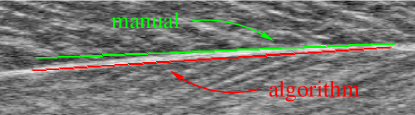

Refer to caption

Figure 4: The aponeurosis curvature in video “W” leads to a small difference in the aponeurosis slope estimation.

In video “W”, the deep aponeurosis was curved slightly (see Fig. 4) and the experts tended to estimate the slope at the right end, whilst the algorithm computed an average slope over its entire width. This had the effect that the automatic estimate of its slope angle was on average one degree greater than the expert opinion: ICC3=0.7640.7640.764, MAE=1.081superscript1.0811.081^{\circ}, hit=4%percent44\%.

As the decision at which position the tangential angle of the aponeurosis is measured is somewhat arbitrary, we conclude that the aponeurosis slope angle is estimated by our algorithm within the possible accuracy. The difference in slope estimation has no effect for video “R”, but for video “W” it leads to a systematic difference of about one degree for the pennation angle, i.e., the automatically estimated pennation angle in video “W” should be about one degree greater than the manually estimated angle.